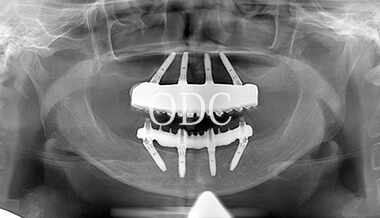

パノラマX線写真

術 後

術前・術後のパノラマX線写真です。上顎(オールオン4)は4本のインプラントにチタンフレームの上部構造が固定されているのがおわかりになると思います。下顎のインプラント埋入部位、上顎のインプラントの本数、再度写真をご覧いただくと、とてもインプラントが埋入されているとわからない程の外観、下顎の残存歯(元々の自分の歯)とも区別がつかない審美性が実現されています。